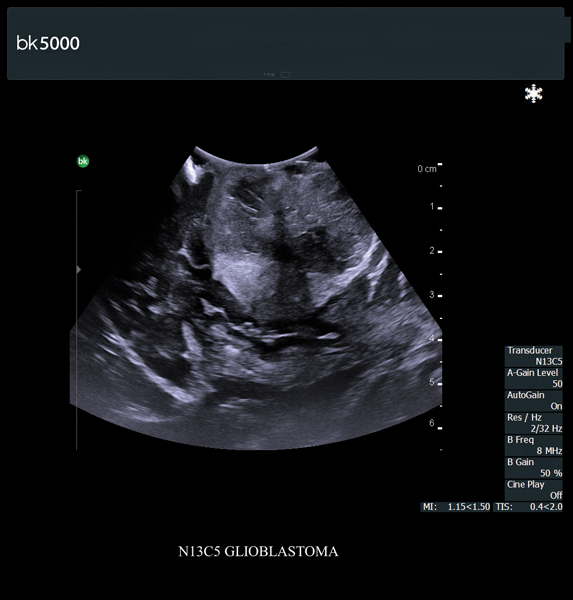

Ultrasound can improve neurosurgical procedures by helping you navigate and identify lesions and anatomical structures in real-time. This is particularly important as the data obtained from a preoperative CT or MRI scan can be outdated at the time of surgery. The bk5000 neurosurgical system provides the highest quality images that allow you to clearly see the margins of a lesion and to determine the best course of action. Using advanced graphics processing technology, this powerful system provides immediate, auto-optimized images that allow you to see the information you need, faster.

Transducers designed for Neurosurgery

The specialized, high-resolution, sterilizable neurosurgery transducers enable you to obtain detailed images of the brain and spinal cord. They have a convenient Smart™ button that lets you activate the transducer, then freeze, store or print the images at the press of a button. Disposable, easy-to-use needle guides assist with targeting lesions.